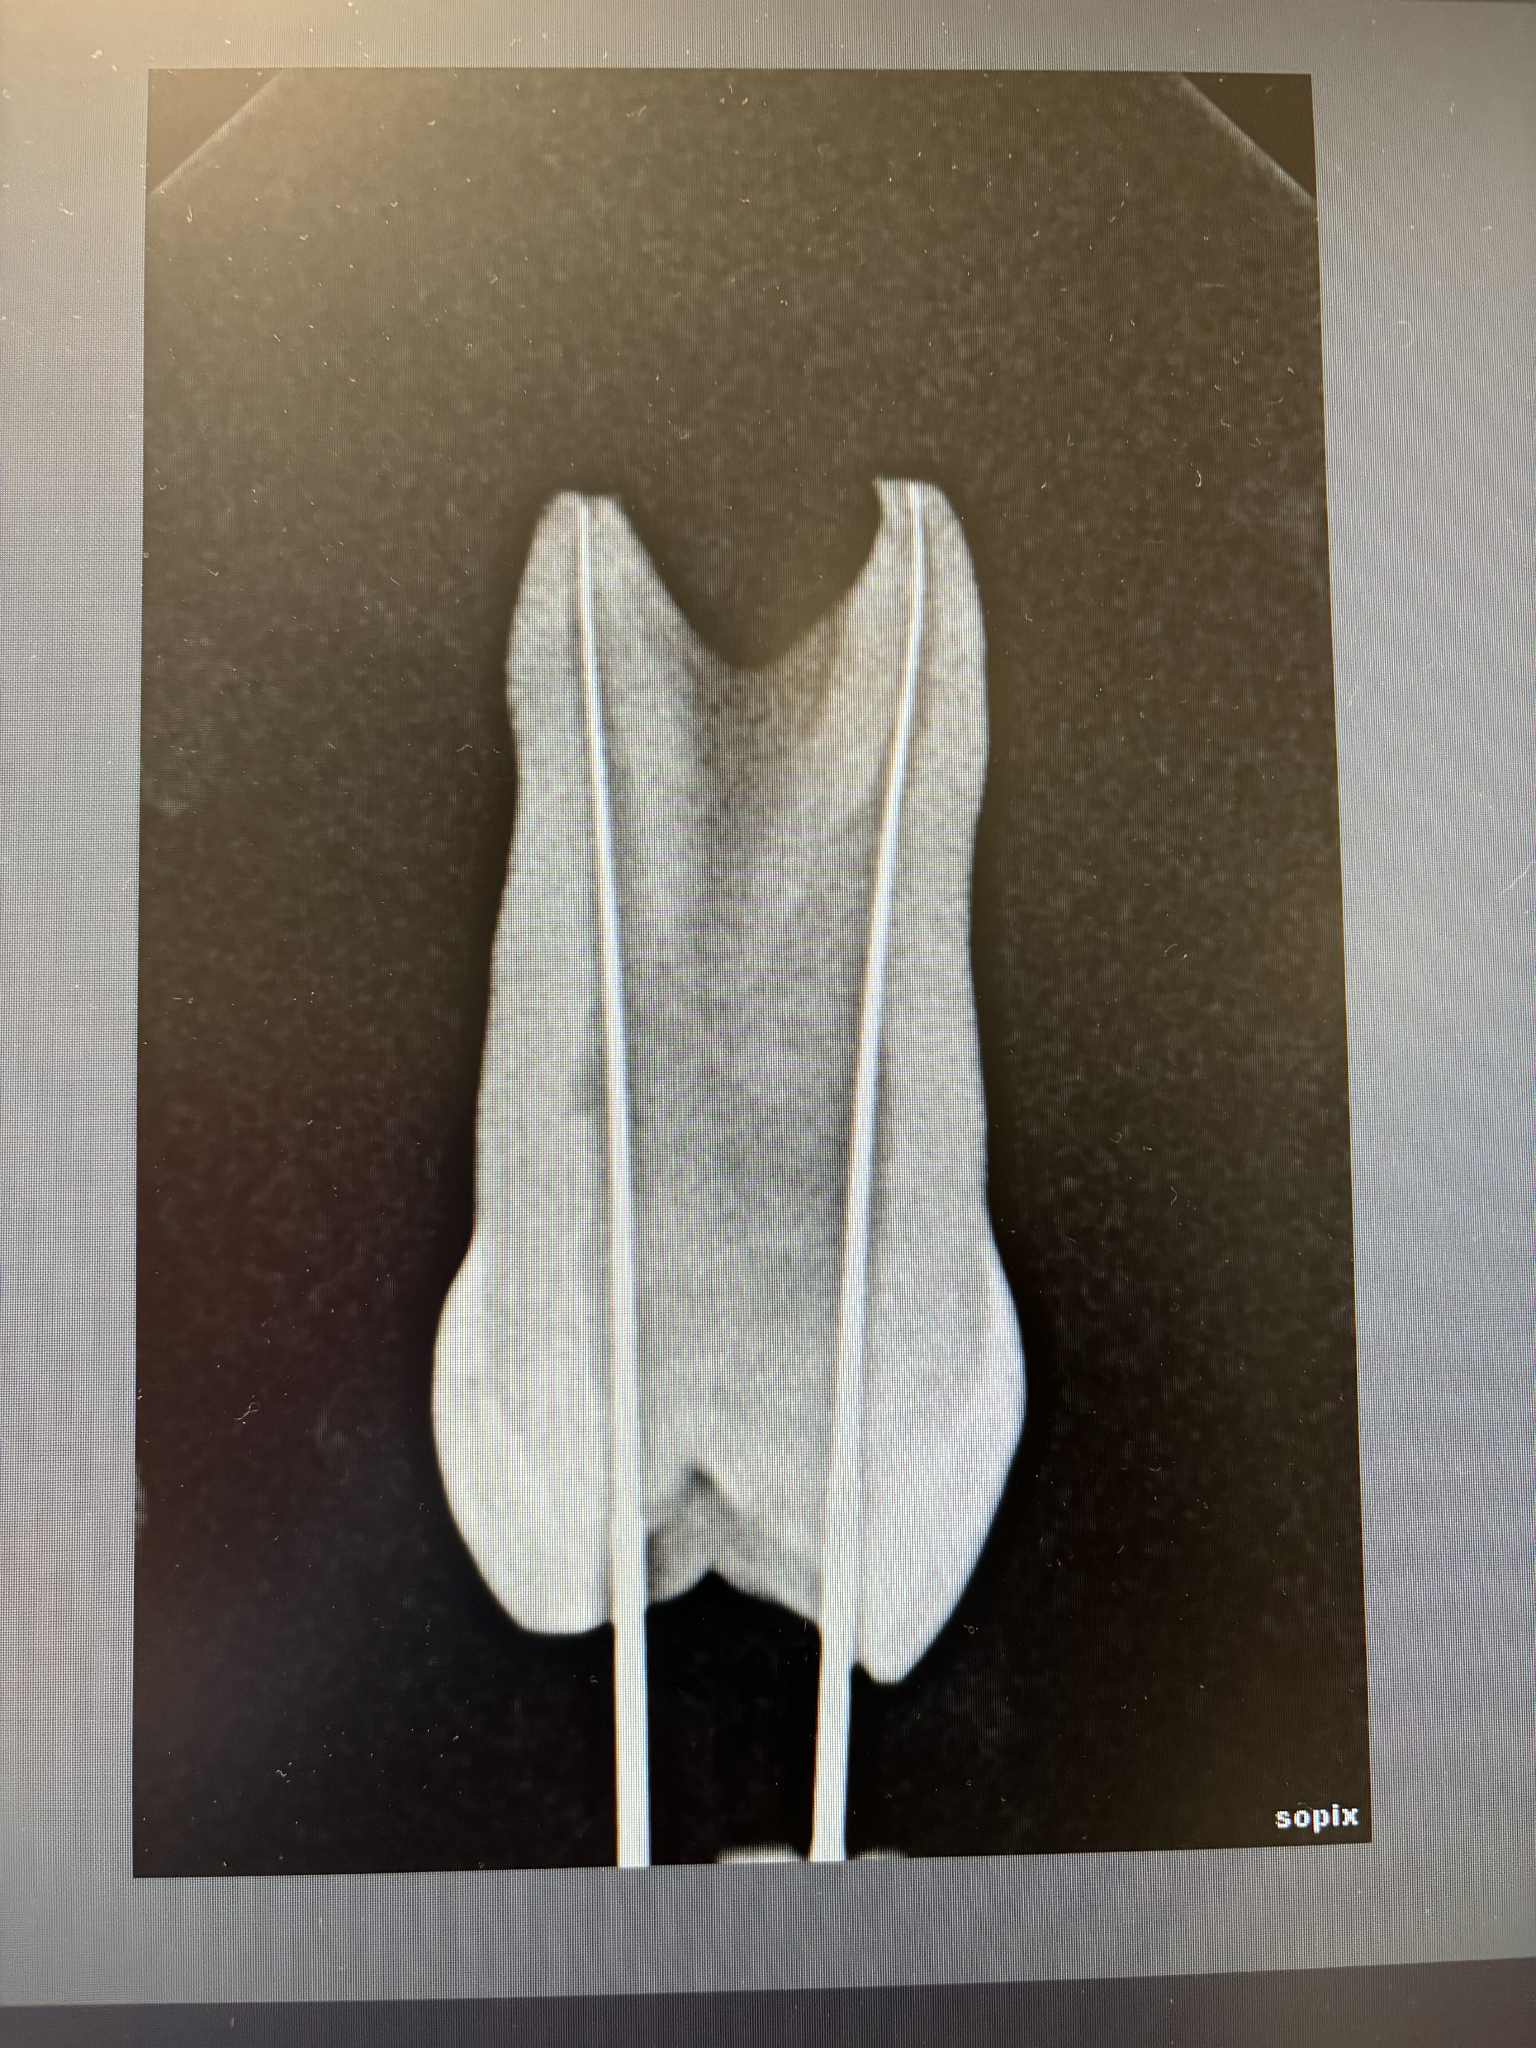

L'odontologie en photo...